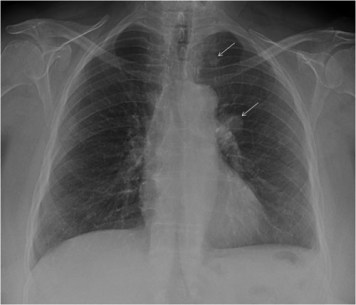

Las figuras 1, 2 y 3 ilustran ejemplos de signo, hallazgo y patrón.

Figura 3. Ejemplo de patrón. La presencia de múltiples nódulos intersticiales, de pequeño tamaño y distribución difusa define al patrón miliar, que puede estar causado por enfermedades granulomatosas infecciosas, y no infecciosas, sarcoidosis, neumoconiosis, metástasis, etc. En este caso se trataba de un paciente VIH + con tuberculosis miliar.